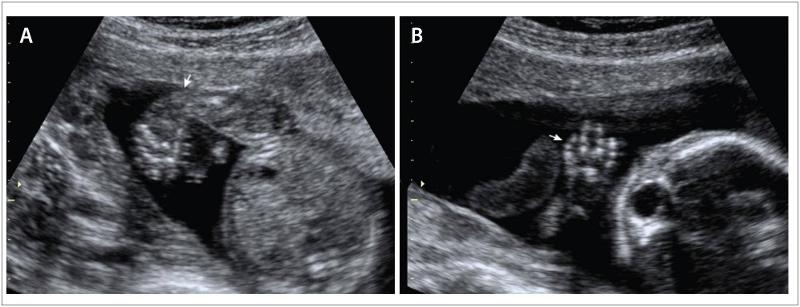

What is Polydactyly?

extra fingers or toes.

Polydactyly

Polydactyly